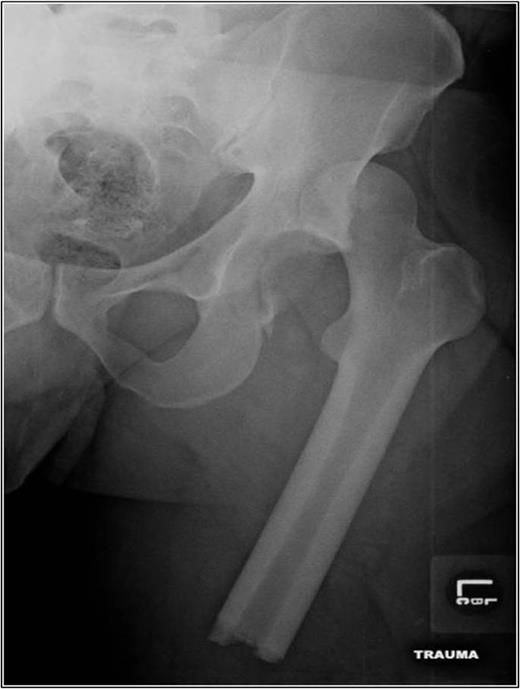

A 35-year-old male was involved in a high-speed urban dirt biking accident. The patient was stable with a GCS of 15 and was neurovascularly intact. His left knee exhibited a 10 × 20 cm medial traumatic arthrotomy and his thigh compartments were soft and compressible. Imaging revealed a left hip postero-superior dislocation, posterior wall acetabular fracture, ipsilateral transverse femoral diaphyseal fracture and an engaging hill-sachs-type lesion of the femoral head with the postero-superior acetabulum (Figs 1–3). Cefazolin, gentamicin and tetanus prophylaxis were administered along with a bedside washout of the traumatic arthrotomy. The patient was medically cleared for operative intervention as all blood work and further imaging were normal.

AP left femur of type B floating hip with associated hip dislocation. The medial knee soft tissue injury is also appreciated.